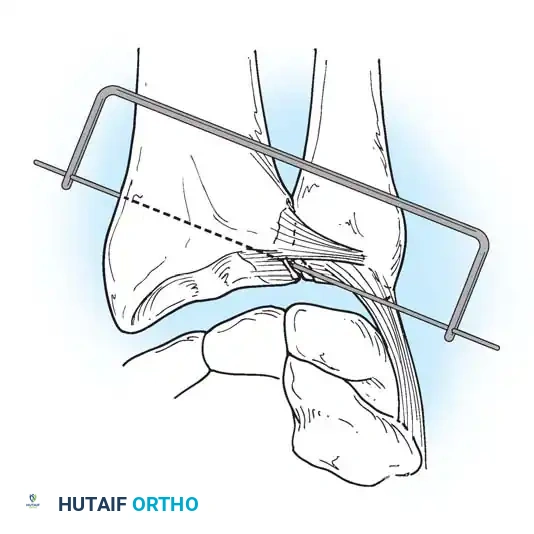

In cases of severe instability or concomitant ECU subsheath disruption, open capsular repair and ECU stabilization are required.

Open repair of the dorsal capsule and TFCC, ensuring robust closure and stabilization of the ulnar-sided structures.

Stabilization of the ECU tendon and subsheath, a critical step in addressing complex ulnar-sided wrist trauma.

If the DRUJ remains unstable after soft tissue repair, temporary transarticular K-wire fixation may be necessary to protect the repair during the initial healing phase.

Radiographic confirmation of temporary transarticular K-wire fixation stabilizing the DRUJ following complex TFCC repair.